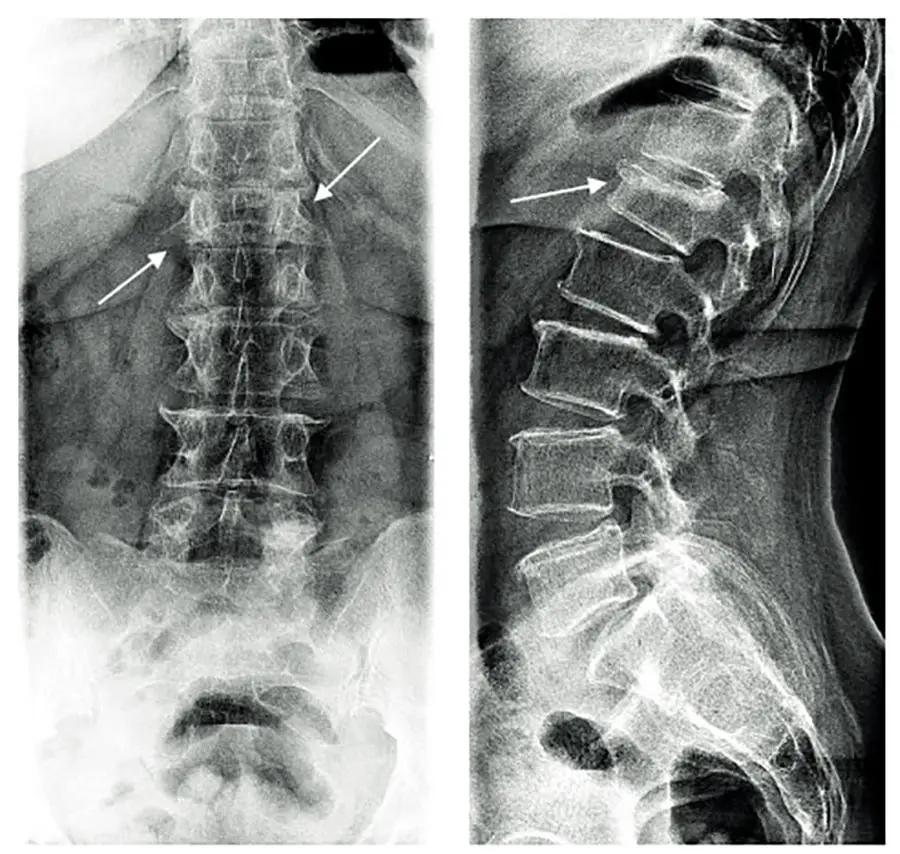

По направлению от врача-невролога сделали рентген пояснично-крестцового отдела позвоночника. Диагноз — компрессионный перелом первого поясничного позвонка.

Такой перелом происходит из-за сдавливания (компрессии) позвоночного столба. Травма может произойти в самых обычных ситуациях: при подъеме тяжестей, тряске в машине, прыжке или падении с небольшой высоты. В группе риска пациенты с остеопорозом, люди пожилого возраста, со слабыми мышцами спины.

При компрессионном переломе возникает трещина или разрыв кости позвонка. Возможно образование осколков, травма спинного мозга во внутреннем канале позвоночника.